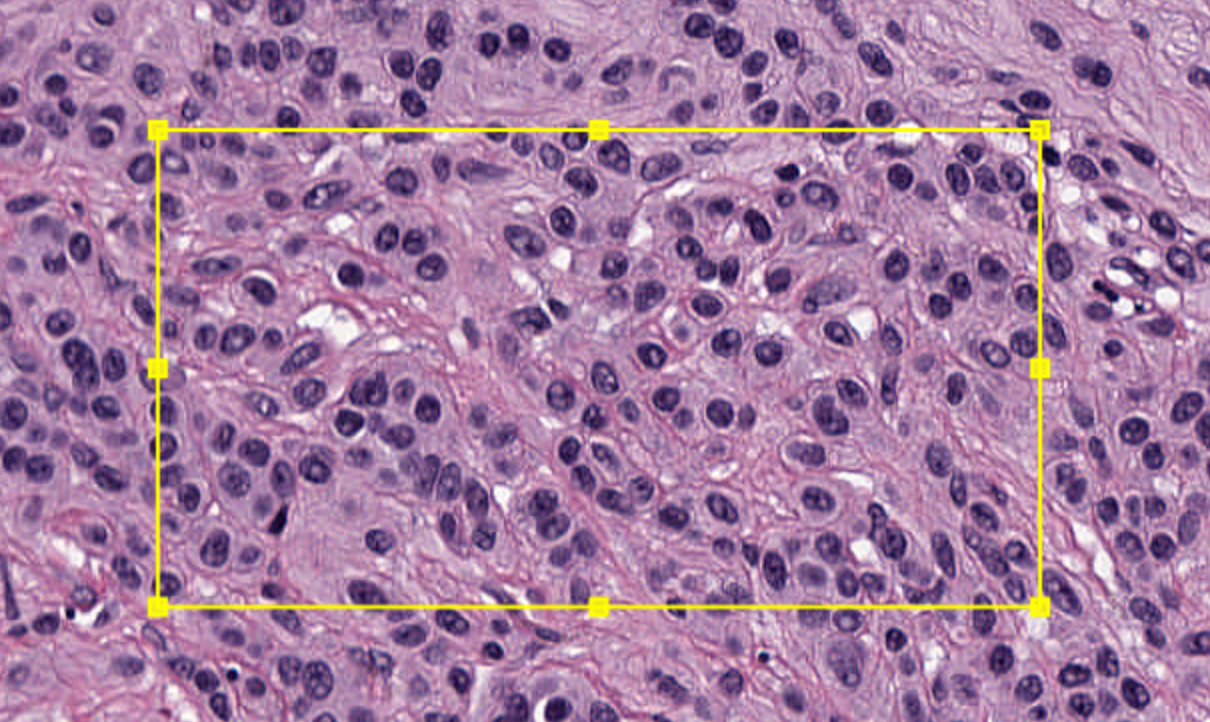

2-4:绘制注释

通过在图像顶部绘制一个矩形来创建您的第一个注释对象。

首先,点击矩形工具 …/…/images/RECTANGLE_TOOL.png 来选择它,然后点击并拖动图像中的一个区域。释放鼠标按钮时,矩形应该仍然显示在图像顶部。

现在尝试使用椭圆 、多边形 和画笔工具 在图像的不同区域绘制几个不同形状的注释。

QuPath的大多数绘图工具工作方式类似(即选择工具,点击图像,拖动鼠标),但请注意多边形工具还允许您避免拖动,而是点击多边形的每个顶点位置。双击以设置最后一个点。

2-5:识别选择

您应该发现,当您绘制一个注释对象时,它最初是被选中的。在上面的屏幕截图中,选中的(多边形)注释显示为黄色 - 带有小方块手柄表示可以调整的顶点。

通常,您希望在进行某些操作之前确保对象已被选中。如果当前没有选中您想要的对象,请返回到移动工具 ,通过点击工具按钮或按M键,然后双击它以进行选择。

提示

默认情况下,选择显示为黄色。您可以在“Edit ‣ Preferences…”中更改此颜色。您还可以关闭使用选择颜色,在这种情况下,QuPath会寻找其他方式来显示对象是否被选中,例如通过加粗轮廓或围绕它绘制一个框。

2-9:检测细胞

接下来,尝试在注释内部创建检测对象。首先,在图像中包含细胞的区域绘制一个注释——最好是相当小的区域,包含大约100个细胞。